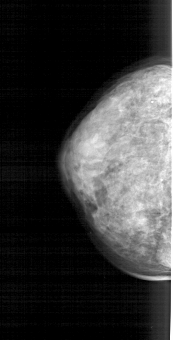

A_1660_1.LEFT_MLO

LEFT_MLO LINES 5041 PIXELS_PER_LINE 2476 BITS_PER_PIXEL 12 RESOLUTION 43.5 NON_OVERLAY